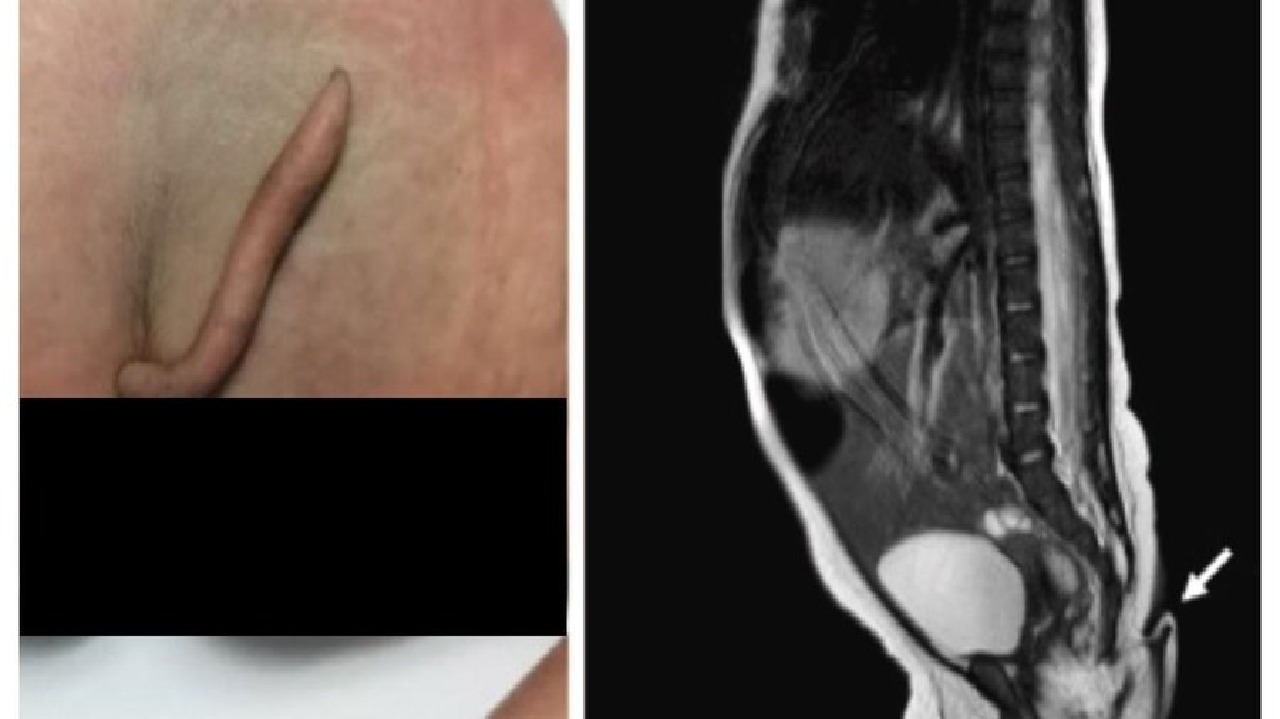

ولادة طفلة بذيل طوله 6 سم في حالة نادرة